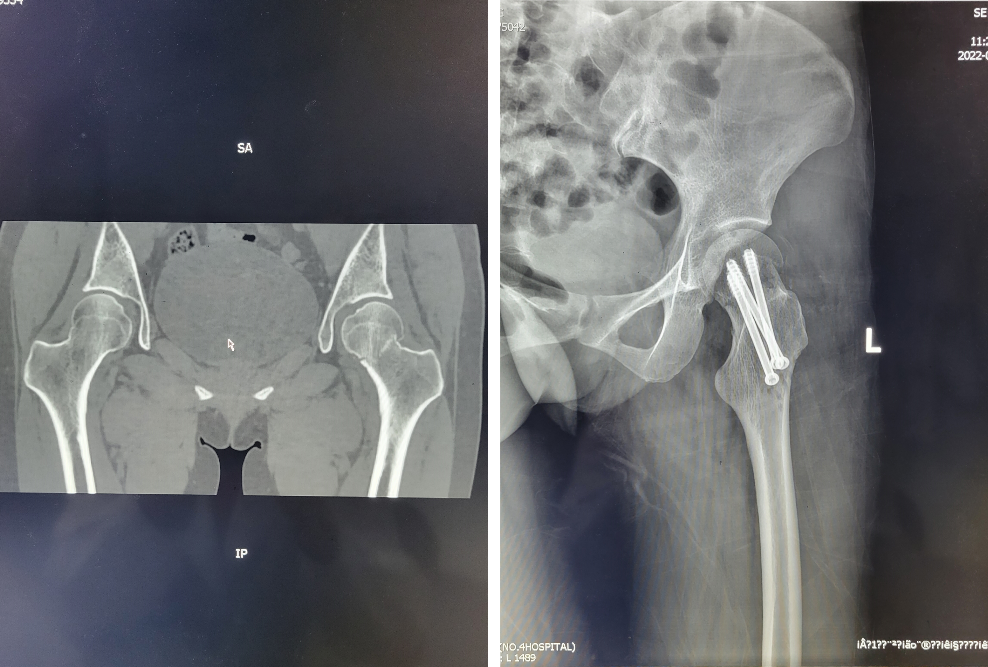

典型病例:女性患者,35岁,因跌倒致左侧髋部疼痛、活动障碍1周入院,入院诊断为左侧股骨颈骨折,急诊行保髋治疗(股骨颈骨折闭合复位空心拉力螺钉内固定+带血管蒂髂骨瓣移植术),术后股骨颈骨折解剖复位,股骨头血供良好。

2.股骨颈骨折闭合复位空心拉力螺钉内固定+带血管蒂髂骨瓣移植术

针对年轻的股骨颈骨折患者,我院也常规开展保髋治疗,以期保留及挽救股骨头功能,延缓或者避免后期行人工髋关节置换术。青壮年股骨颈骨折多系高能量损伤所致。早期手术进行骨折解剖复位及坚强内固定,并应用显微外科技术转移带血管蒂骨瓣重建头颈血运,以及术后正确的康复训练对股骨颈骨折患者至关重要。